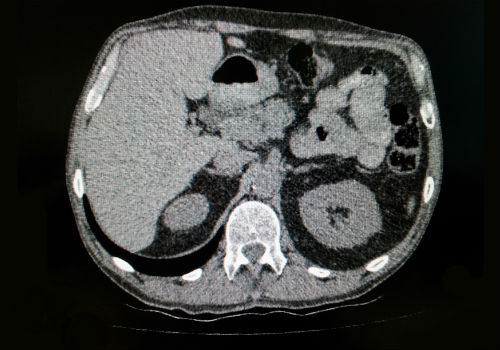

- МРТ и КТ,

Мрт диагностика является одним из наиболее высокоинформативных способов уточнения состояния паренхиматозных органов. При проведении МРТ либо КТ диагностики подтверждается, либо полностью исключается развитие медленного процесса формирования карцином.

Чтобы визуализировать состояние панкреатических протоков и оценить степень их поражения при проведении МРТ выполняется процедура ЭРХПГ, также в некоторых ситуациях может проводиться ангиографическое исследование сосудистых волокон поджелудочной железы.